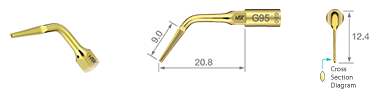

G95

Z217705

TiN kaplama / 0.7 mm kalınlık

Root extraction

(upper left No. 2 tooth removal)

Impacted tooth

(lower left No. 8 tooth removal)